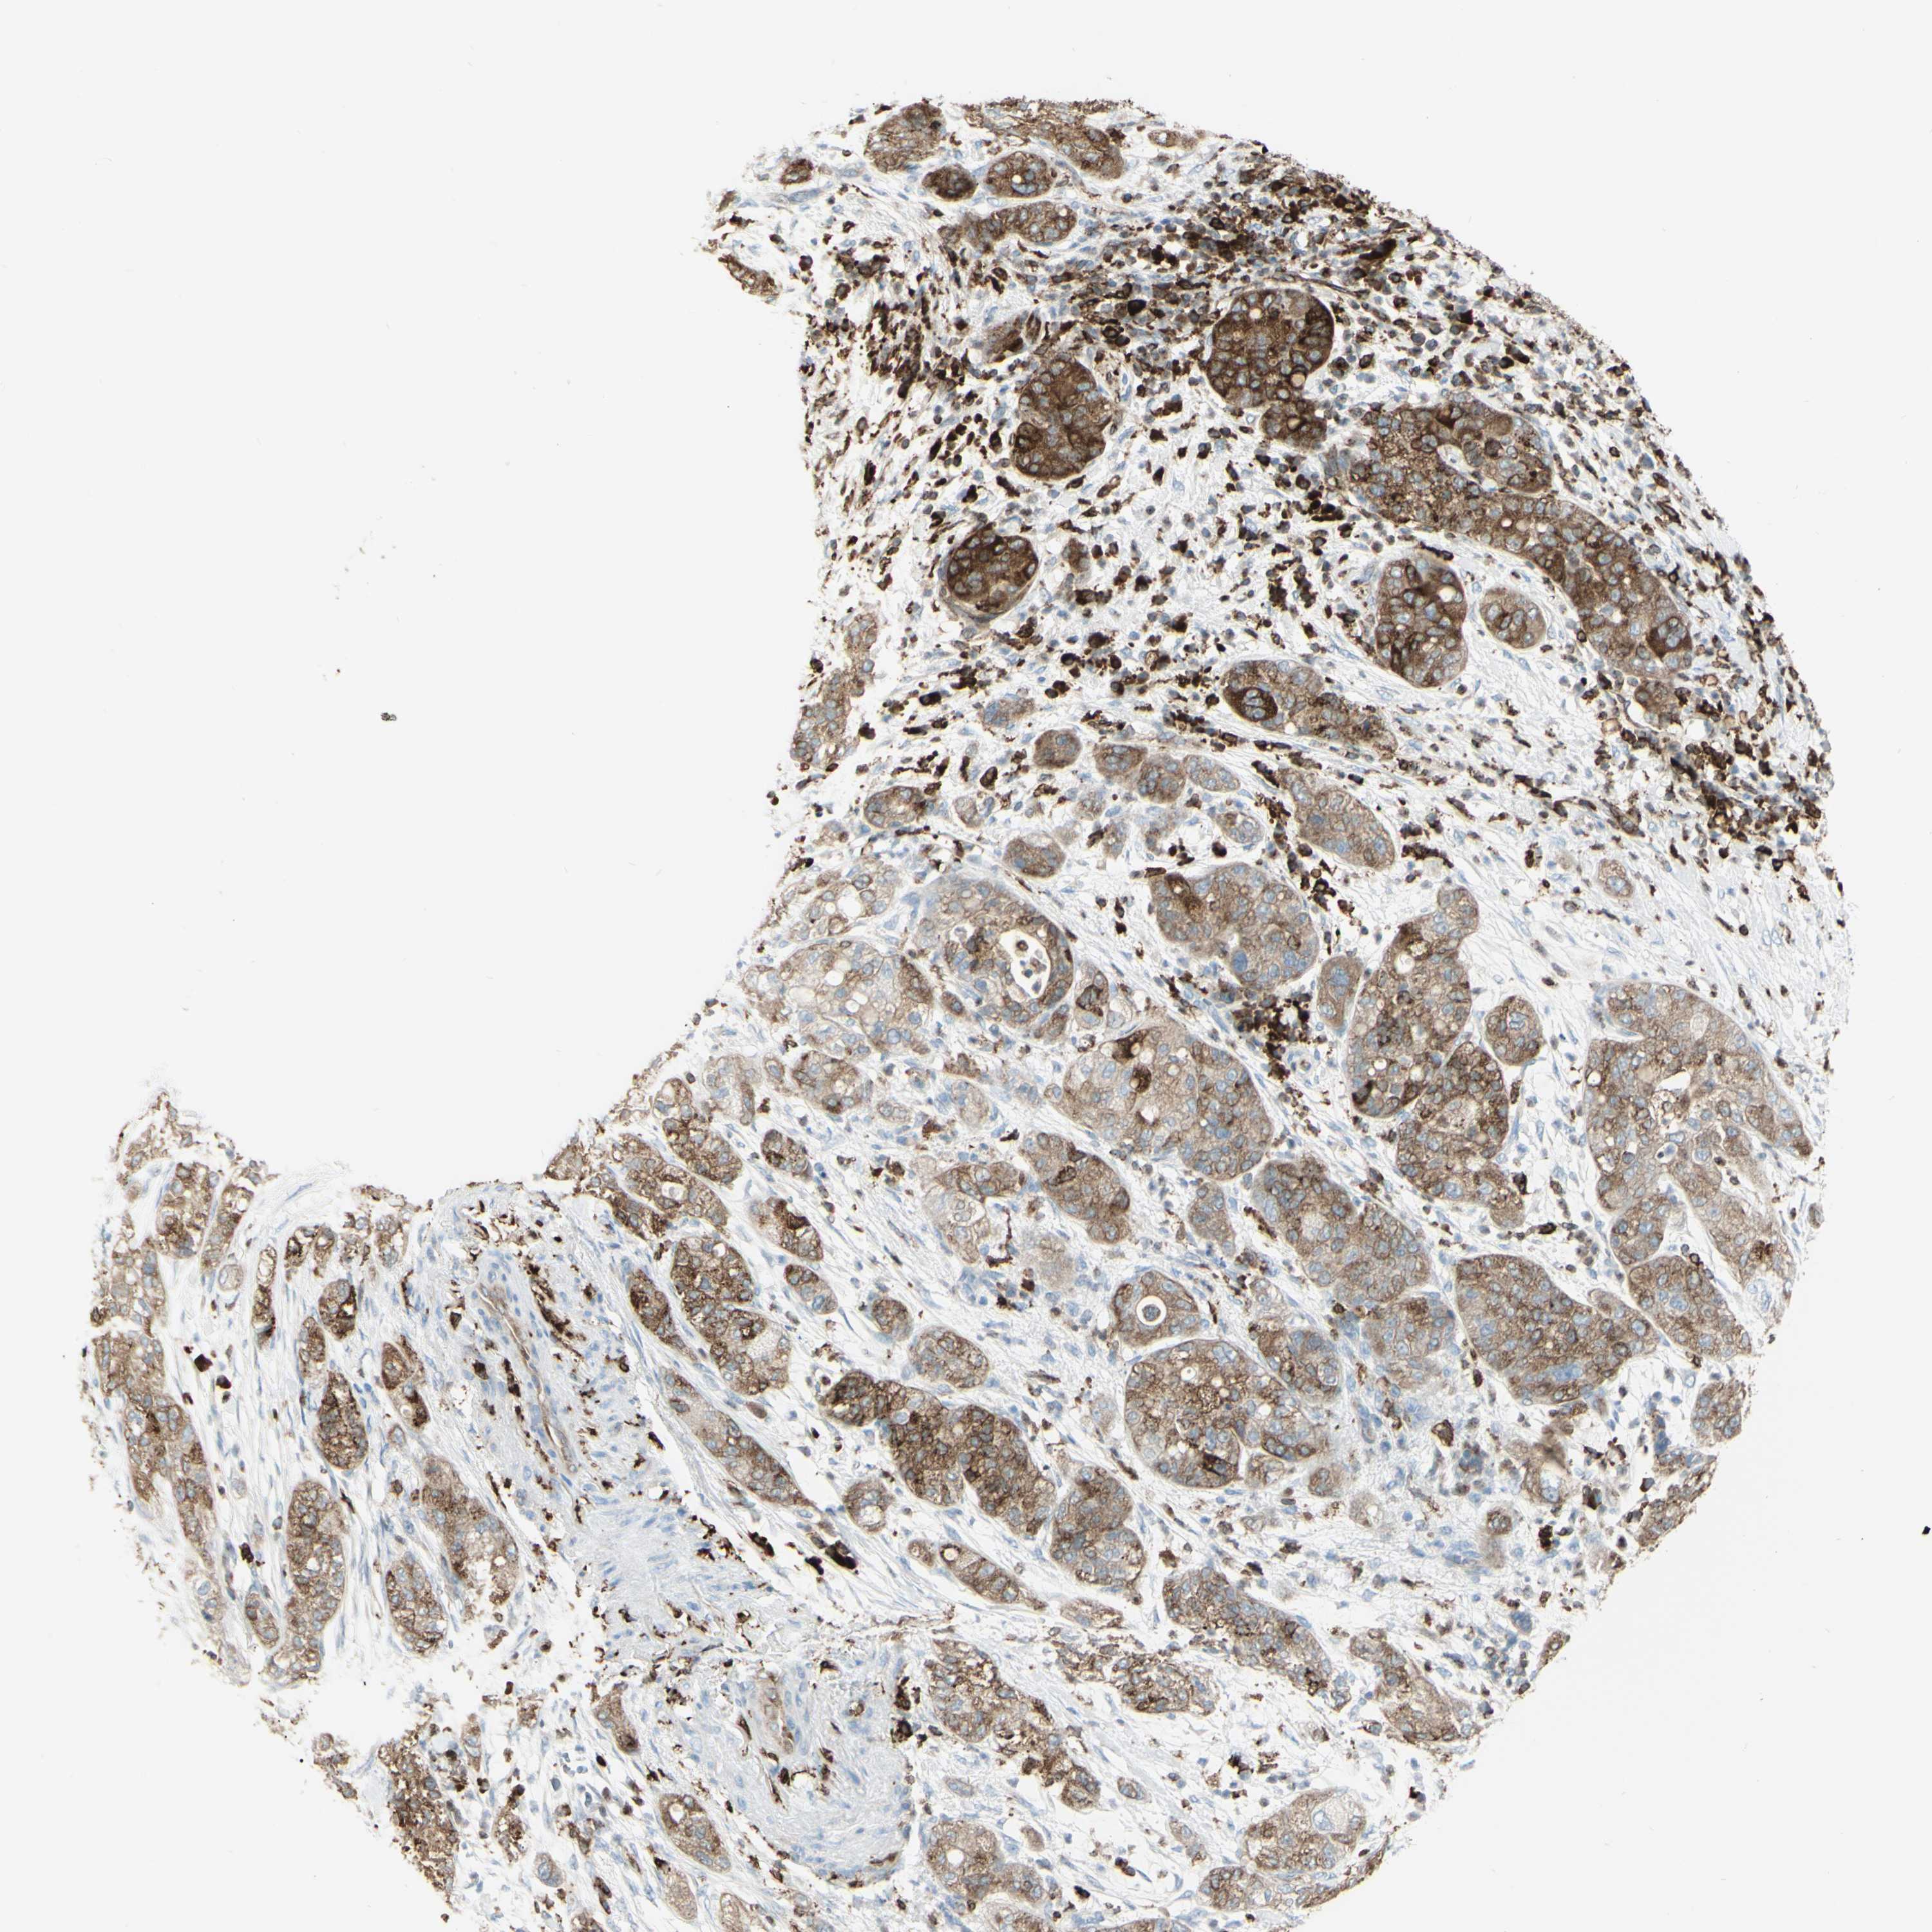

PANCREATIC CANCER - Protein expressioni

A mouse-over function shows sample information and annotation data. Click on an image to view it in a full screen mode. Samples can be filtered based on level of antibody staining by selecting one or several of the following categories: high, medium, low and not detected. The assay and annotation is described here.

Note that samples used for immunohistochemistry by the Human Protein Atlas do not correspond to samples in the TCGA dataset.

Antibody stainingi

Antibody staining in the annotated cell types in the current human tissue is reported as not detected, low, medium, or high, based on conventional immunohistochemistry profiling in selected tissues. This score is based on the combination of the staining intensity and fraction of stained cells.

Each image is clickable and will lead to virtual microscopy that enables deeper exploration of all samples and also displays staining intensity scores, fraction scores and subcellular localization as well as patient and tissue information for each sample.

Antibody HPA010592

Antibody CAB002506

Antibody CAB079994

Staining

High

Medium

Low

Not detected

Intensity

Strong

Moderate

Weak

Negative

Quantity

>75%

75%-25%

<25%

None

Location

Nuclear

Cytoplasmic/membranous

Cytoplasmic/membranous,nuclear

Adenocarcinoma, NOS

Adenocarcinoma, metastatic, NOS